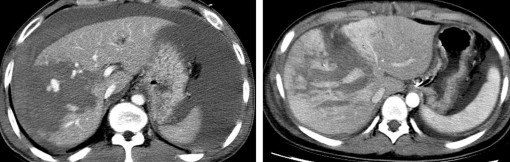

Hình 1.14: CTG độ I. Rách nhu mô: đường vỡ sâu < 1cm (mũi tên).

Nguồn: Shanmuganathan K, Mirvis SE [21].

Hình 1.15: CTG độ II. Rách nhu mô sâu 1-3 cm, dài < 10 cm (mũi tên).

Hình 1.16: CTG độ II. Tụ máu dưới bao gan 10–50% diện tích bề mặt.